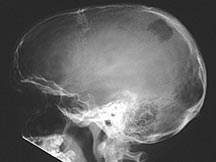

- Any bone but 90% have skull involvement

Sites:

- Skull